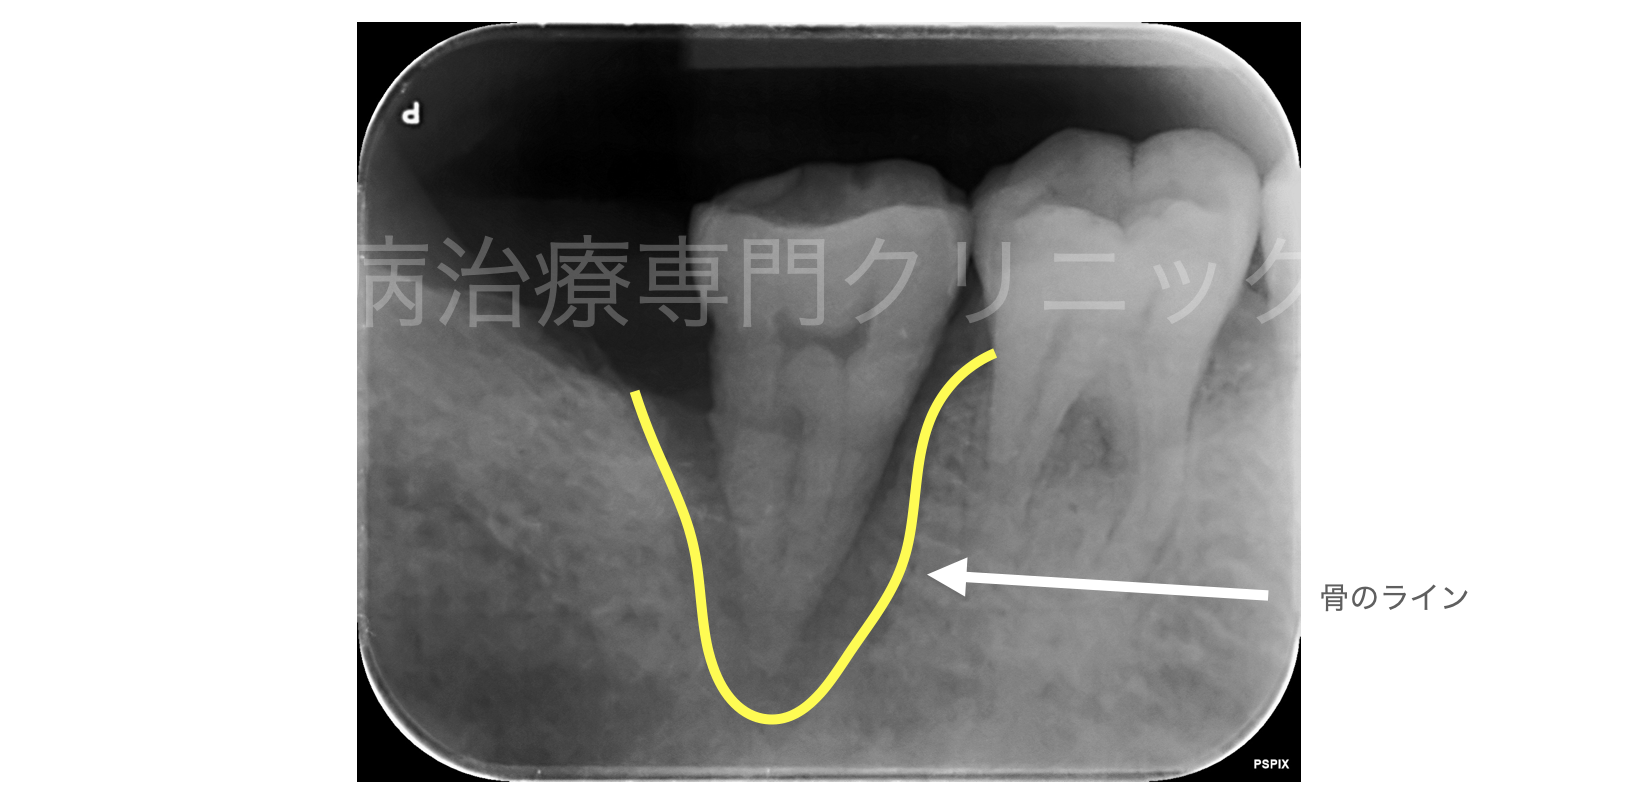

大阪梅田のインプラント歯周病専門歯科 SPIDO(スピード)

日本初の欧米と同基準の 歯周病および インプラントの 専門治療をお届けします